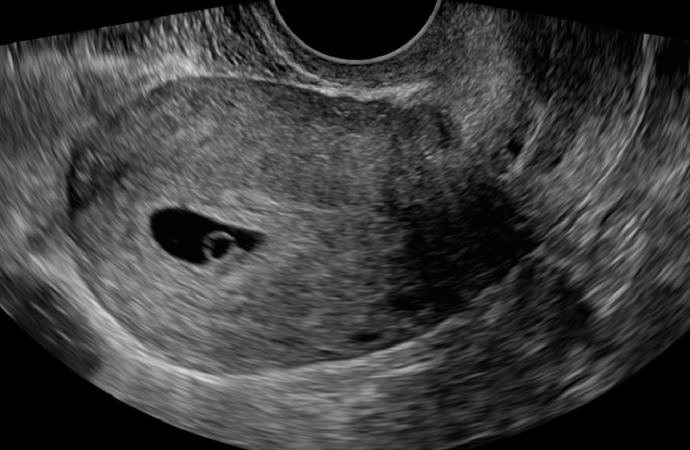

- 01 초음파검사

- 자궁 내 정상 임신 및 태아 심장 박동 확인

- 자궁 내 정상 착상 여부와 태아의 심장 박동을 확인해 임신의 시작을 안정적으로 진단합니다.

- 자궁 내 정상 착상 여부 확인

- 태아 심박동 확인

- 자궁/난소 이상 확인